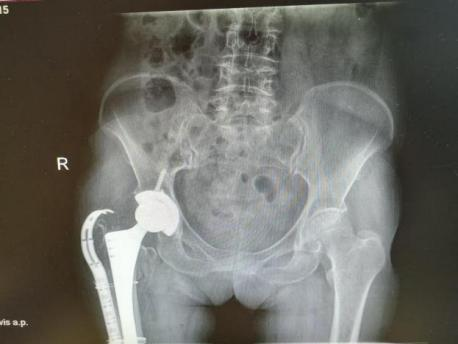

多年来,贵州航天医院各科室紧跟医学前沿,不断强技术、补短板,大力开展新技术、新项目,完成了许多高精尖、高难度、本地区“首例”的技术,填补了医院医疗技术空白,满足了群众日益增长的医疗需求。 贵州航天医院骨科率先在遵义地区开展骨搬移技术,截至目前,已治愈慢性骨髓炎、感染性骨不连、骨缺损、脉管炎、糖尿病足患者200余例,糖尿病足治疗保肢率达到98%。 本期,我们将为大家带来骨科特色技术——骨搬移技术(Ilizarov)。 案例分享 一名59岁的患者,身患糖尿病12年,在来我院3个月前出现了右脚溃烂的症状,来院就诊时,患者的右脚十分红肿,右脚脚趾坏死,伤口处不断流出黑红色脓液,情况十分严重。在接诊到患者时,骨科专家团队高度重视,立刻为患者完善了CT血管造影(CTA)等相关检查,诊断为:2型糖尿病,糖尿病周围血管病变,右糖尿病足。 术 前 考虑到患者情况比较严重,为最大限度保证患者肢体完整,科室专家团队进行了严格的讨论评估,为患者制定了骨搬移技术治疗方案,在征得患者及其家属的同意后,成功通过搬移骨块为患者进行治疗,促进患者病变肢体血管再生。 胫骨横向骨搬移外架固定 清除感染病灶 术后调节外架,通过搬移骨块 促进患肢血管再生 患者在术后三周前来换药,观察到感染得到进一步控制;术后六周复查,患者病变处已愈合,进行CT血管造影(CTA)后可明显观察到足部血管再生。 术后3周 术后6周愈合 CT血管造影见足部血管再生 糖尿病患者全身与局部的问题互为影响,形成恶性循环,糖尿病足溃疡创面迁延不愈,常见干性坏疽、湿性坏疽、趾坏死、深且大的溃疡以及骨髓炎等症状,还可导致脓毒血症,以往为保全生命,患者被迫选择一次或多次截肢。骨搬移技术的发展进步,能在血糖有效控制、局部有效清创下,有效促进患肢微血管再生,改善患肢血供,达到糖尿病足更快治疗康复的目的,并能根据病变情况最大限度的保障患者肢体完整。 什么是骨搬移技术 骨搬移技术是通过使用专用的骨外固定器固定骨段,每天缓慢牵拉,在牵拉搬移过程中,骨段尾部形成新骨及新的软组织,从而修复骨骼缺损及软组织缺损。是治疗大段骨缺损、骨不连、骨感染、肢体畸形的金标准方法,也用于治疗脉管炎、糖尿病足等肢体缺血性疾病。 骨感染缺损 切除感染段 搬移骨段 新骨形成 骨感染根治愈合 骨搬移技术原理 生物组织在持续、稳定、缓慢牵拉下,能刺激细胞分裂、组织再生,骨外固定技术运用该原理,通过持续缓慢调节外固定器形成牵拉张力,促进牵引成骨与相邻组织再生,如神经、血管、肌肉、皮肤等再生,达到治疗大段骨缺损、肢体缺血如糖尿病足等疾病的目的。 骨搬移技术优势 (一)除治疗骨缺损、骨不连外,有更广的适用范围,利用组织再生、血管再生等特性,能大量运用于肢体畸形的矫形、糖尿病足等的治疗。 (二)治疗效果确切,重建肢体外型和功能,极大降低截肢率和残疾率。 (三)明显提高了患者生活质量,极大减轻其家庭及社会负担。 肢体畸形的矫形 慢性骨髓炎 骨段切除 术后1年 濒临截肢的脉管炎术后6周 难愈创面术后3周 贵州航天医院骨科 专家团队 赵学平 骨科主任 主任医师 临床擅长:从事骨科临床工作30余年,对骨科常见疾病的诊治具有丰富的临床经验。 世界中医药联合会脊柱康复专业委员会常务理事,中华中医药学会整脊分会常务委员,中国中西医结合学会骨伤科分会肢体矫形功能重建与康复专家委员会常务委员,中国研究性医院学会骨科创新与转换专业委员会关节外科学组保髋工作委员会常委,中国康复技术转化及发展促进会骨外科与康复技术转化专业委员会常务委员,泛珠三角区域运动医学联盟(PPRD-SMA)理事会常务理事,中国研究型医院学会运动医学专业委员会委员,贵州省中医药学会整脊分会副主任委员,贵州省中西医结合学会银质针专业委员会副主任委员,贵州省康复医学会骨与关节专业委员会常务委员,贵州省人民医院骨科专科联盟常务理事,贵州省康复医学会骨内科专业委员会常务委员,中华医学会贵州省骨科学会委员,贵州省康复医学会脊柱脊髓专业委员会常务委员,贵州省运动医学分会委员,贵州省康复医学会骨与软组织肿瘤专业委员会委员,遵义市医学会创伤分会副主任委员,贵州省康复医学会骨内科专业委员会遵义地区分会常务委员,遵义市医疗事故鉴定、伤残鉴定、工伤鉴定、司法鉴定专家。 长期从事骨科临床研究及教学工作,在国家级、省部级杂志发表论文20余篇,SCI论文2篇,参与主编骨科专著2部,主持省部级科研项目2项,参与指导省部级、市级科研项目6项。 陈明勇 骨科副主任 副主任医师 临床擅长:从事创伤骨科工作约20年,对骨缺损、骨不连、骨肿瘤、肢体畸形等的肢体矫形重建及功能重建,慢性化脓性骨髓炎的根治治疗、糖尿病足的保肢治疗、快速康复理念(ERAS)下的老年骨折的诊治,四肢复杂骨折的诊治,四肢骨折等微创手术治疗具有丰富的临床经验。 2004年毕业于遵义医学院临床专业,曾在中国人民解放军总医院、广西医科大学第一附属医院、上海第六人民医院骨科进修。中国中西医结合学会骨伤科专业委员会横向骨搬移治疗糖尿病足及微血管网再生学组首届委员,遵义市医学会创伤分会常务委员。 瞿 辉 骨科 副主任医师 临床擅长:对骨科的常见病、关节外科、脊柱外科及运动医学疾病的诊治具有丰富的临床经验,熟练掌握骨科手术操作技术。 毕业于遵义医学院临床医学系,2005年前往广州中山大学第一附院骨显微医学部进修学习,2011年前往成都华西医院进修学习,并多次在省内外学习骨科相关知识,是中华医学会骨科分会会员。 赵兴东 骨科 主任医师 临床擅长:擅长骨科的常见病及各种创伤、四肢骨折创伤修复、骨感染、手足疾病的诊治和手足体表畸形的矫形整复,熟练掌握骨科四肢骨病及创伤的手术操作技术,尤其在四肢关节复杂性损伤、手足外伤、组织缺损创面、难治创面的皮瓣修复方面及平足、高弓足矫形方面及四肢慢性疼痛诊治、康复方面具有丰富的临床经验。 硕士研究生,毕业于遵义医学院临床外科系,2015年前往山东省立医院手足外科进修学习;遵义市医学分会创伤分会第一、二届委员,遵义市手外科医学会第二委届员会常务委员;在省级及省级以上期刊发表文章9篇,参编著作2部,参与主持并完成市级课题1项,参与市级课题2项、省级课题1项。 张俊凯 骨科 副主任医师 临床擅长:从事骨科临床工作28年,对创伤骨折、骨感染、骨缺损、骨不连等外科诊治,四肢骨折的微创手术治疗,四肢复杂骨折(如关节内粉碎性骨折、多发骨折等)的损伤控制及手术治疗等具有丰富的临床经验。 1995年毕业于遵义医学院临床专业,2009年前往复旦大学附属医院骨科进修1年。 卢懿明 骨科 副主任医师 临床擅长:从事骨科工作18年,对创伤骨折、四肢骨折的微创手术治疗、四肢复杂骨折(如关节内粉碎性骨折、多发骨折等)的损伤控制及手术治疗,尤其是髋部骨折的PFNA等微创技术,踝关节骨折、膝关节周围骨折的Mipo微创技术等具有丰富的临床经验,开展了4项新技术,发明6项新型专利技术。 2005年毕业于遵义医学院临床专业,2017年,前往南方医科大学第三附属医院骨科进修半年,回院后运用Mipo技术对骨干骨折及干骺端骨折的治疗技术,同时积极开展骨盆骨折、髋臼骨折腹直肌外侧切口的应用;发表了多篇专业论文,经常参与省内外学术交流会授课,获得医院荣誉称号多个。 邬夏荣 骨科 副主任医师 临床擅长:从事骨科工作16年,对四肢复杂骨折、骨肿瘤的诊治,尤其是足踝创伤、慢性踝关节损伤、平足症等诊疗具有丰富的临床经验。 2006年毕业于遵义医科大学临床医学专业,曾在陆军军医大学西南医院进修学习,发表多篇骨科学术论文。 余德怀 骨科 副主任医师 临床擅长:从事骨科工作10余年,对运动医学、骨关节、脊柱外科常见病、多发病的诊治具有丰富的临床经验。 硕士研究生,2011年毕业于遵义医学院临床医学专业,曾前往遵义医科大学附属医院运动医学专业进修学习;是贵州省医学会运动医学分会青年委员,西部关节镜联盟委员;发表多篇骨科学术论文。 冯 乾 骨科 副主任医师 临床擅长:从事骨科工作近20年,熟练掌握骨科多发病及常见病的诊治,尤其对脊柱退变性疾病的诊断及治疗具有丰富的临床经验,主要研究脊柱微创相关治疗方式,能熟练开展椎间孔镜及VBE。 曾前往北京大学第三医院进修学习疼痛及椎间孔镜、首都医科大学友谊医院专业进修脊柱内镜;是贵州省康复医学会第三届脊柱脊髓专业委员会委员;发明专利3项、发表脊柱外科专业论文多篇。 张艳金 骨科 副主任医师 临床擅长:从事骨外科工作16年,对复合伤、多发伤的救治、四肢骨干骨折、关节周围骨折、骨肿瘤、骨髓炎等诊治具有丰富的临床经验。 中共党员,硕士研究生,2006年本科毕业于山西医科大学第二临床医学院,2011年研究生毕业于北京军区总医院;在“老年COPD患者合并髋部骨折的诊治”国际合作课题组研究两年,在老年髋部骨折的诊治方面具有丰富的经验,并发表论文6篇;承担遵义市级课题1项;承担遵义医科大学的临床教学工作,获得遵义医科大学优秀带教老师荣誉。编撰有《骨科疾病诊疗精粹》一书,开展2项新技术,编撰地方规范《务川自治县创伤骨科常见疾病诊疗规范》一书。 赵小锋 骨科 副主任医师 临床擅长:从事骨科临床工作11年,对骨科常见病、多发病诊疗有较为丰富的临床经验,擅长脊柱相关疾病诊断及治疗,尤其是颈、腰、腿疼痛疾病诊断及治疗,擅长胸腰椎骨折微创经皮穿刺内固定术、经皮穿刺椎体成形术、经皮穿刺脊柱内镜下腰椎间盘摘除术、单纯开创腰椎间盘摘除术、腰椎滑脱复位椎间植骨椎融合内固定术、腰椎管狭窄减压融合内固定术及人工髋、膝关节置换术等。 2012年毕业于遵义医学院外科学专业硕士研究生,2019年参加“遵义市115医学人才精英计划”于上海交通大学第一附属医院培训学习,2023年于北京大学第三人民医院脊柱外科进修学习,曾获得遵义市优秀医师荣誉称号。 遵义市手外科第一届委员,遵义市医学会创伤分会第一届委员,遵义市医学会创伤分会第二届委员,贵州省康复医学会第三届脊柱脊髓专业会委员,遵义市医学会烧伤与整形外科学分会委员,发表论文5篇,其中国家级核心期刊1篇,SCI论文1篇,主持市级课题1项并结题,参与市级课题2项。 贵州航天医院骨科简介 基本情况 贵州航天医院(原3417医院)骨科组建于1968年,前身是以创伤和断肢(断指)再植闻名于世的上海市第六人民医院骨科,中国断肢(断指)再植的奠基者、中科院院士陈仲伟等著名专家、学者多次莅临科室指导医疗、教,是贵州省最早拥有专业骨科技术科室之一,在70年代开展了贵州省首例断肢(断指)再植手术。组建50余年来,诊治患者已逾百万,挽救了无数的伤病员,成为了保障遵义地区人民群众健康的重要支撑。 经过几代人的不懈努力,今天的骨科,已由创伤骨科发展至骨病、骨肿瘤、骨结核等领域,现有脊柱外科、关节外科、四肢创伤、手足外科四个亚专科,成为了集医疗、教学、科研于一体的综合学科,是贵州省临床重点专科、遵义市临床重点专科、遵义市骨科临床医学中心、遵义市基层骨科专科联盟理事长单位。 科室目前开放床位110张,共有医护人员50余人,副高级以上专家18人,硕士研究生15人。拥有一流骨科医疗设备多台,每年不定期选派优秀技术骨干到全国各大知名医学院校进修、学习、参观、交流,并邀请国内、国外知名专家教授来院进行交流、指导,通过不断引进国内外先进的诊疗技术,科室医疗技术水平稳步提升,为广大人民群众提供了优质的医疗服务。 专科特色 骨一科 (一)骨缺损、骨不连的肢体与功能重建 胫骨横向骨搬移技术治疗糖尿病足: (二)慢性骨髓炎的根治治疗 (三)肢体缺血性疾病如糖尿病足、脉管炎的保肢治疗 (四)皮瓣修复 (五)复杂创伤的治疗 (六)老年髋部骨折及小儿骨折快速手术 老年髋部骨折: 骨二科 (一)胸腰椎骨折微创经皮椎弓根螺钉固定术 (二)老年性骨质疏松性患者腰椎滑脱脊柱内固定术(骨水泥螺钉) (三)V形双通道脊柱内镜技术(VBE)腰椎融合术治疗腰椎退行性疾病 (四)老年性骨质疏松性骨折(PVP/PKP)术 (五)人工髋关节置换术 (六)双侧股骨头坏死人工全髋关节置换 (七)右侧全髋置换术后假体周围骨折翻修 (八)人工膝关节置换术 (九)人工膝关节假体松动翻修 (十)关节镜技术 传统手术切口 关节镜技术切口 诊疗范围 骨一科 1.四肢创伤、矫形。 2.手、足踝外科。 骨二科